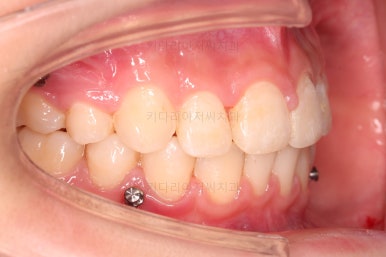

연산동치아교정 선택한 장치는 엠파워 클리어라고 하는 자가결찰 세라믹 장치입니다.

치아 갯수를 맞추고 튀어나온 앞니를 넣기 위해서 윗니 중간의 작은 어금니를 발치를 했고요.

아래는 통째로 앞으로 끌고 나오기로 했습니다.

아래턱은 아쉽게도 성장 시킬 수 있는 나이는 지났고, 대신 가능한 선에서 아랫니를 앞으로 빼보기로 했습니다.

윗니는 틈을 점점 줄여가고요.

아랫니는 중간에 오히려 틈이 생기고 있죠?

이런 효과로 위아래 앞니는 급속도로 가까워지게 됩니다.

아랫니는 이후에 어금니를 앞으로 당겨오면서 빈공간을 줄여 나갑니다.